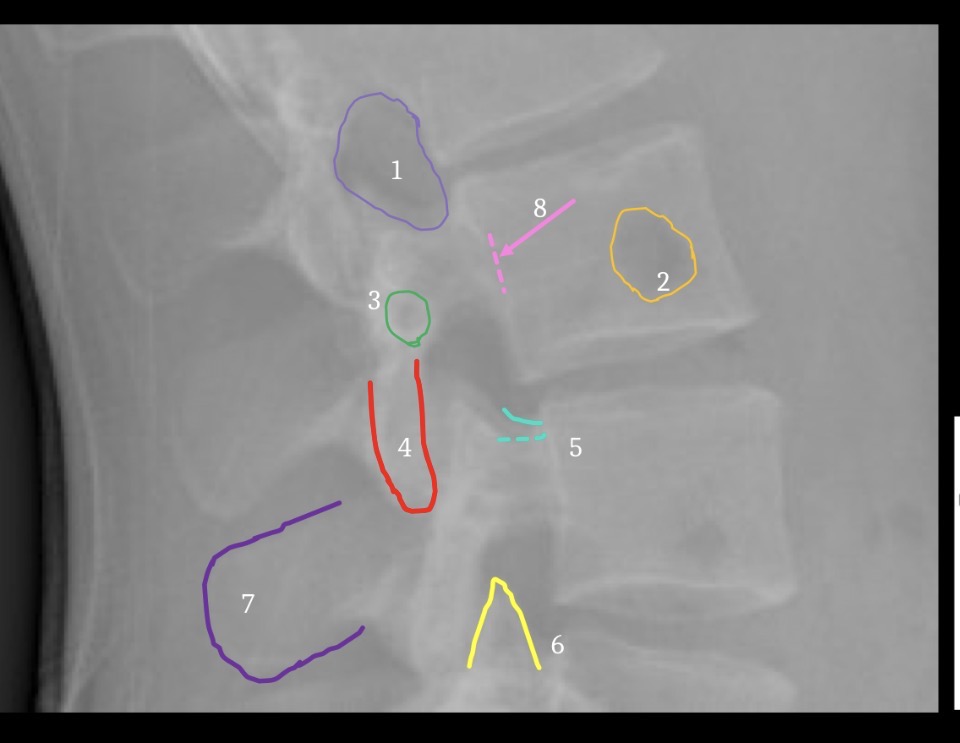

4

Inferior articular process

5

Superior margin of pedicle

6

Superior articular processes

8

Vascular channel

Interlaminar space

Lamina

Superior endplate, anterior margin

7

Superior endplate, posterior margin

9

Accessory tubercle

11

Mammillary Process